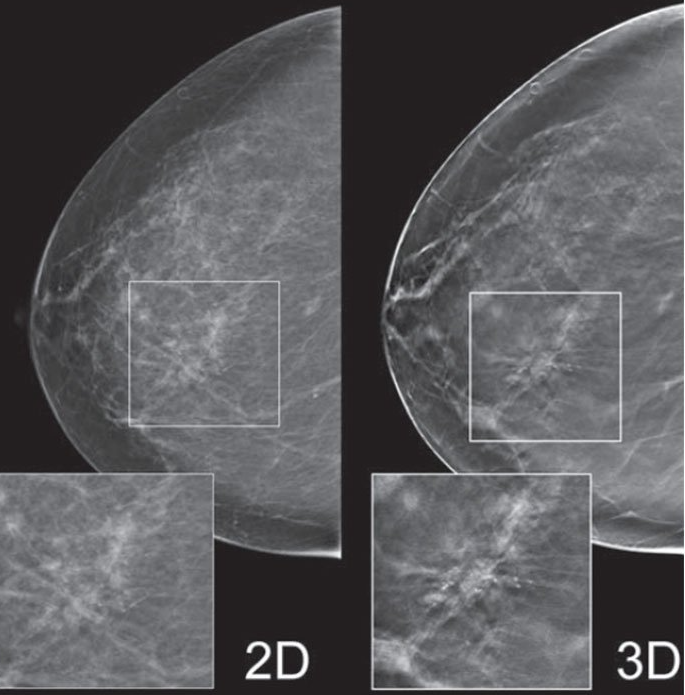

Lo studio radiologico del Dott. Famiglietti Gianfranco, specialista in radiologia diagnostica si occupa di ecotomografia, mammografia e densitometria ossea. I nostri macchinari sono tutti di ultima generazione per garantire ai nostri pazienti il miglior risultato con l'esposizione alla quantità di radiazioni più bassa possibile.

L'altissima qualità dei nostri macchinari ci permette di eseguire esami di ottima qualità in prima battuta riducendo al minimo la necessità di ripetizione e quindi ancora una volta l'esposizione del paziente a radiazioni inutili.